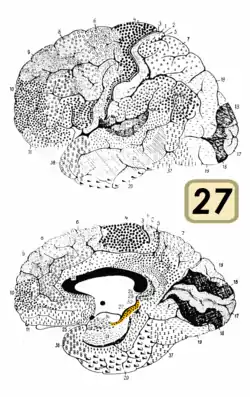

| Brodmann area 27 | |

Area 27 of Brodmann-1909 is a cytoarchitecturally defined cortical area that is a rostral part of the parahippocampal gyrus. It is commonly regarded as a synonym of presubiculum.[1]